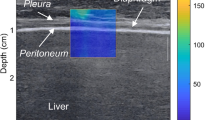

The high-resolution ultrasonic diagnostic apparatus (Aixplorer, Supersonic Imagine, Provence, France) was used, with a 4–15 MHz frequency linear array probe. Each subject was instructed to remain in the left lying position. The physician placed the probe under the rib between the anterior to mid-axillary line and approximately the 6th to 12th intercostal space to allow for the probe to display the diaphragm to the greatest extent (Fig. 1). The gain was adjusted, and the depth was checked. After the image of the right diaphragmatic rib of the examinee became stable, the SWE mode was switched, and the elastic range was adjusted to 0-160 kPa. When the subject was calmly holding their breath at the end of inhalation, the elastic modulus of the diaphragm and intercostal muscles in the ROI (region of interest) was measured by using Q-BOX. When measuring the diaphragm, a circular area with a diameter of 1 mm was selected as the ROI. The elastic modulus of the diaphragm was measured three times, and the average value was taken (Fig. 2). The subject was instructed to move to a supine position, and the physician placed the probe on the intercostal muscles of the front chest wall to obtain images of the intercostal muscles (Fig. 1). The subject was then asked to hold his or her breath at the end of inhalation. After the image became stable, the SWE mode was turned on, and the elastic modulus was measured. The ROI was set to a circle with a diameter of 2 mm, and the average was taken after 3 measurements (Fig. 3). Similar to the measurement method of An [22], the diaphragm excursion (DE) and diaphragm thickening fraction (TF) were measured at tidal inspiration and at maximal deep inspiration. Pulmonary function tests were performed in accordance with the standards of the European Respiratory Society [23], and the FEV1, forced vital capacity (FVC), FEV1/FVC, inspiratory capacity (IC), functional residual capacity (FRC), residual volume (RV), total lung capacity (TLC) and RV/TLC were recorded.